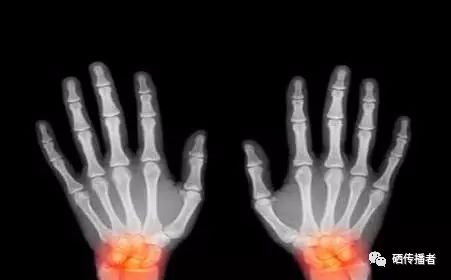

1.硒与心血管疾病

血管壁的老化是心血管疾病发生的重要的因素。之所以中风和猝死的人士以中老年人居多,其中最大的原因就在于人到中老年之后,因为血管壁的逐渐老化导致弹性下降,血管壁变得非常脆弱,所以稍微受到外界的不良影响就特别容易崩溃、出血。而血管老化并非不可阻止,因为促使血管加速衰老的物质就是有害自由基,通过清除自由基,就能延缓血管壁衰老。硒是强抗氧化剂,它能及时的清除体内的有害自由基,防止人体血管老化